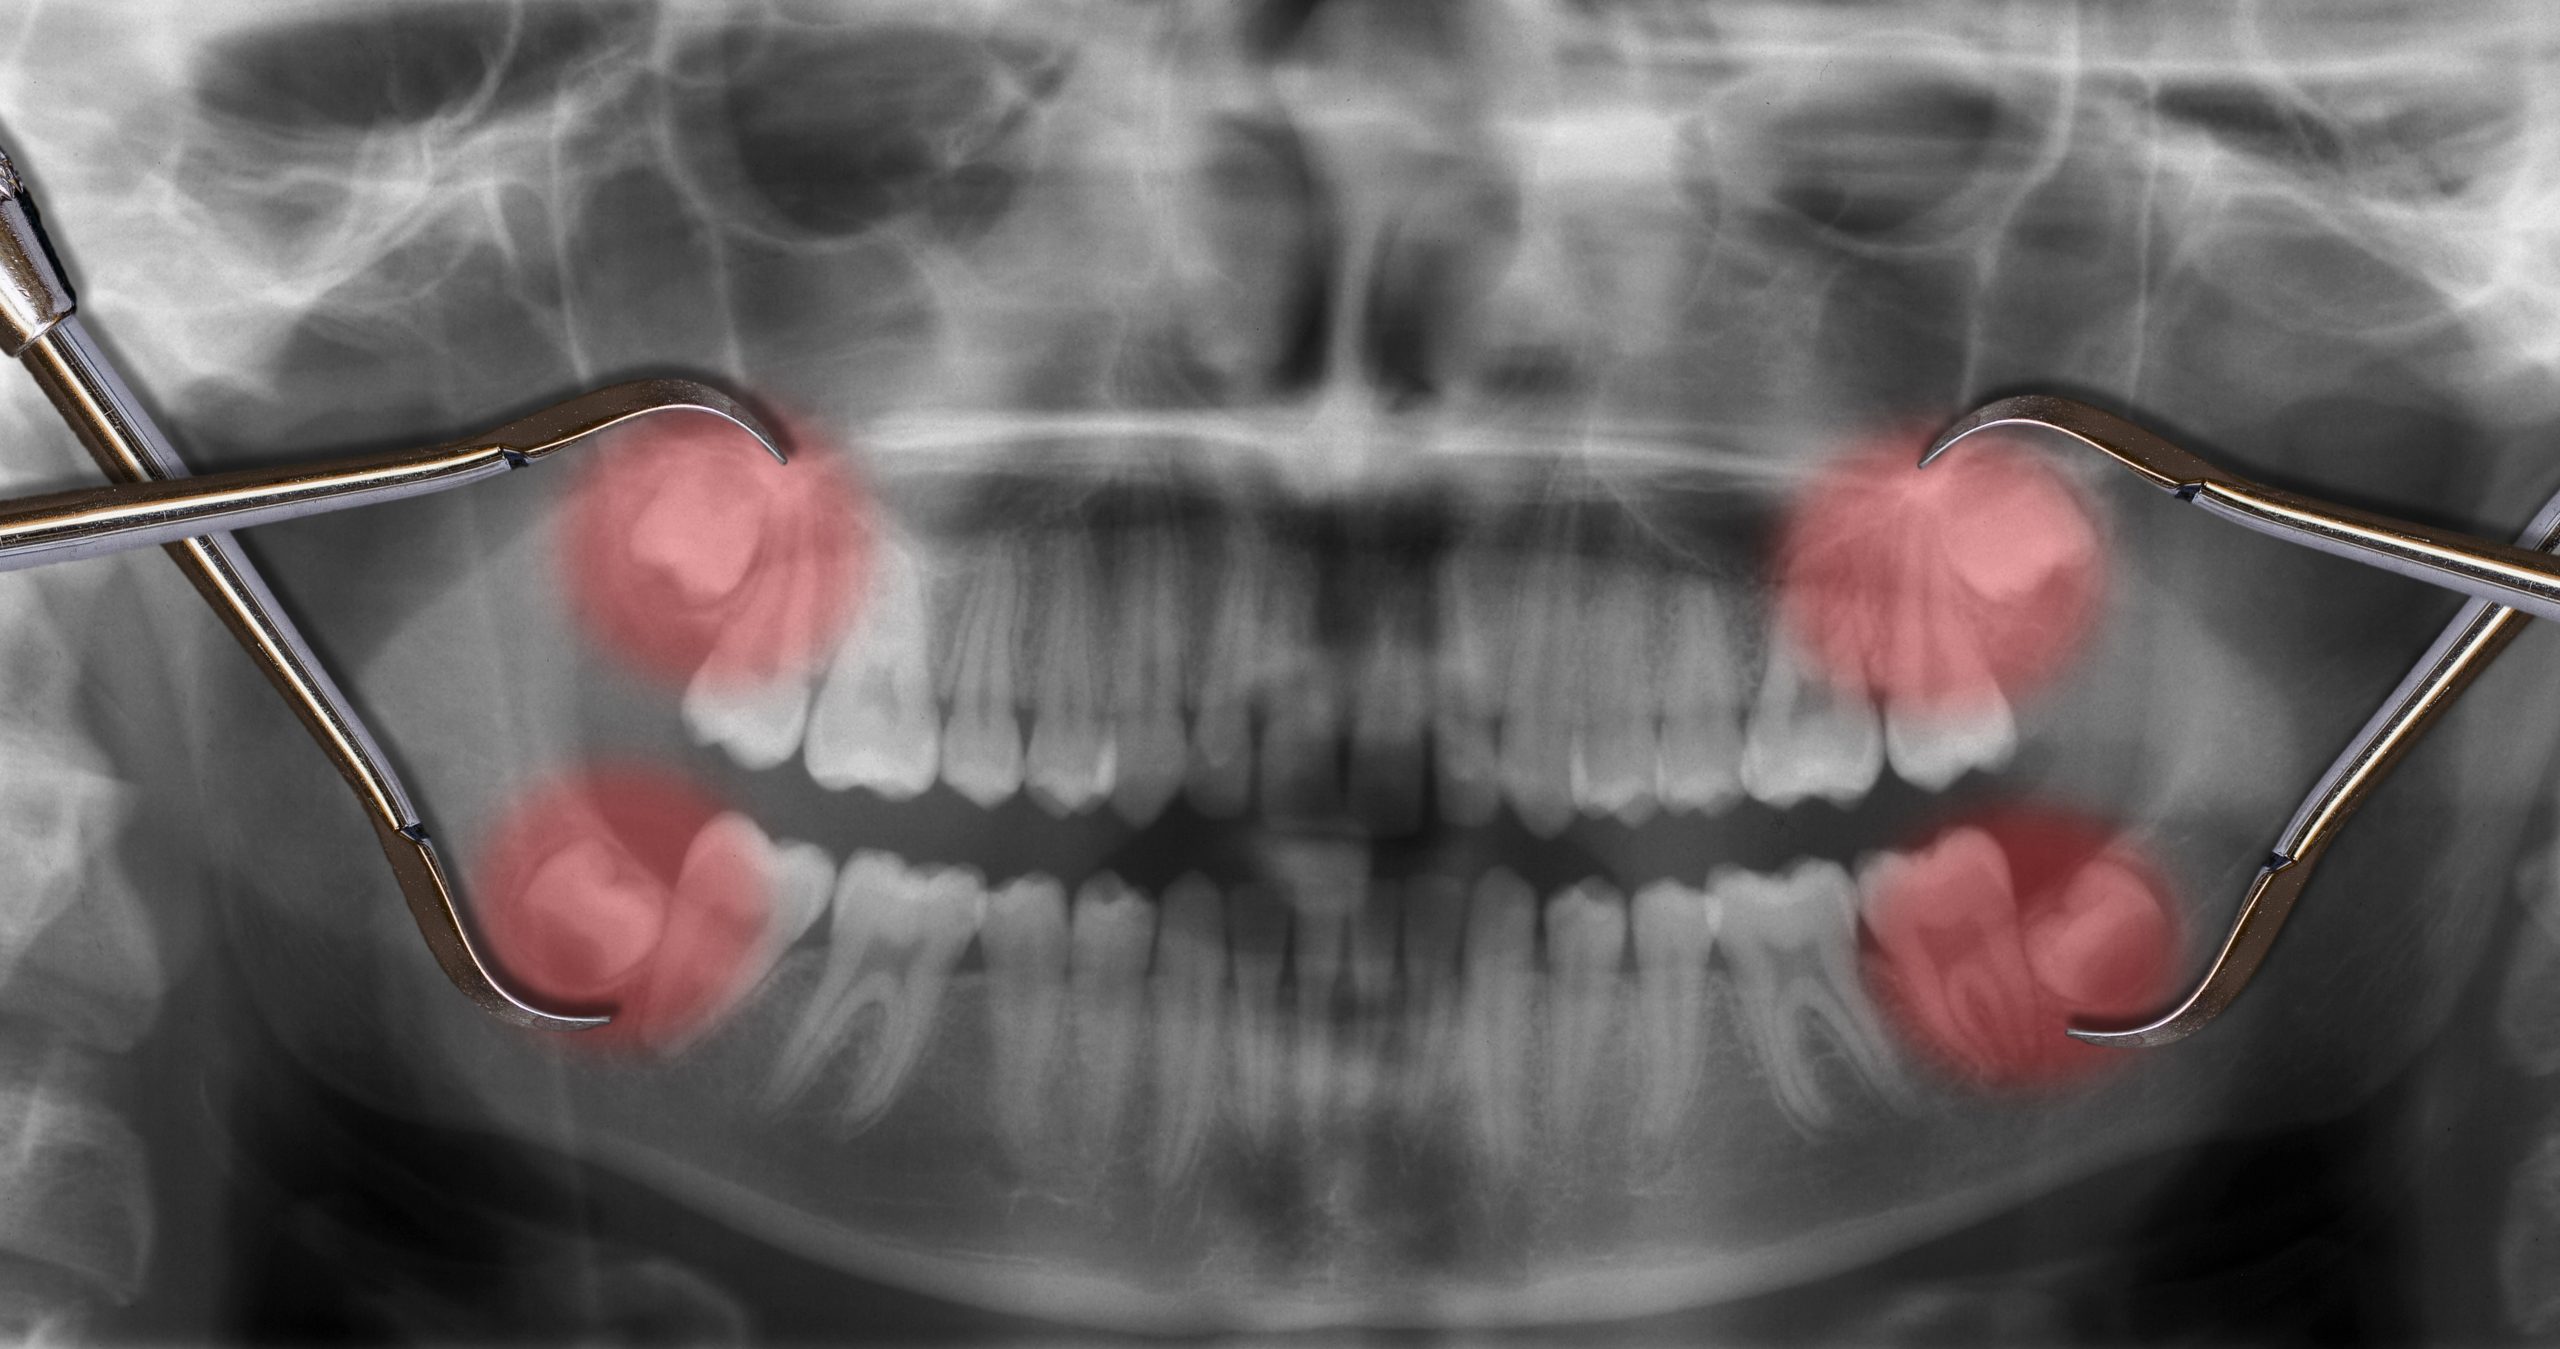

Understanding the basics of a simple tooth extraction procedure is essential for anyone facing this common dental process. This procedure involves the removal of a tooth that is visible in the mouth and can be performed quickly and smoothly by a dental professional. The process typically begins with a thorough examination and X-rays to assess the tooth’s condition and surrounding bone structure. Local anesthesia is then administered to ensure comfort, and the tooth is carefully loosened and removed using specialized instruments.

The simple tooth extraction procedure is often necessary for various reasons, such as decay, damage, or preparation for orthodontic treatment. Understanding the steps involved can help alleviate any anxiety about the process. For those interested in learning more about related procedures, such as creating space for orthodontic work, you can explore our detailed guide on Tooth Extraction for Overcrowding: Make Space for a Straighter Smile.